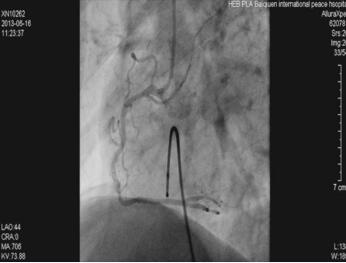

因为患者心电监测呈现持续窦性心动过缓,心率45次/分,遂经右股静脉途径送入临时起搏电极导线至右室心尖部,给予心室起搏,起搏频率60次/分。冠状动脉造影提示:LM及LAD、LCX未见明显狭窄(图1-23-3),RCA中段以远处完全闭塞,血栓负荷较重(图1-23-4)。

图1-23-3 左冠状动脉造影影像

图1-23-4 右冠状动脉造影影像